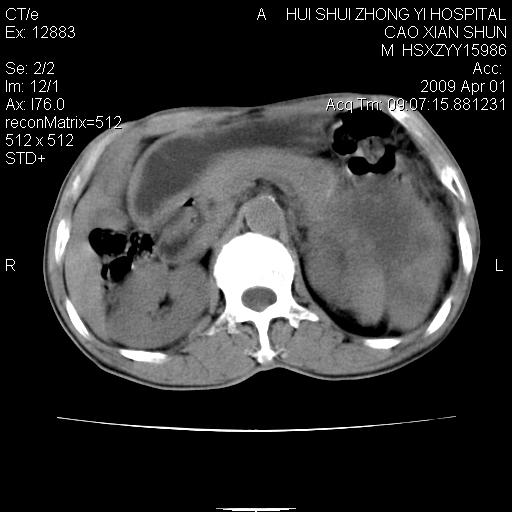

以下是引用随光逐影在2009-4-1 14:23:00的发言:[br]肝、脾多发低密度占位性病变,性质待定(不排除转移瘤可能);建议行进一步检查。

以下是引用liaoqiang在2009-4-1 15:53:00的发言:[br]考虑脾脏肿瘤或胰尾部肿瘤伴肝转移。建议增强。

以下是引用ydx_74在2009-4-1 15:18:00的发言:[br]肝、脾多发低密度占位性病变,考虑转移瘤或淋巴瘤